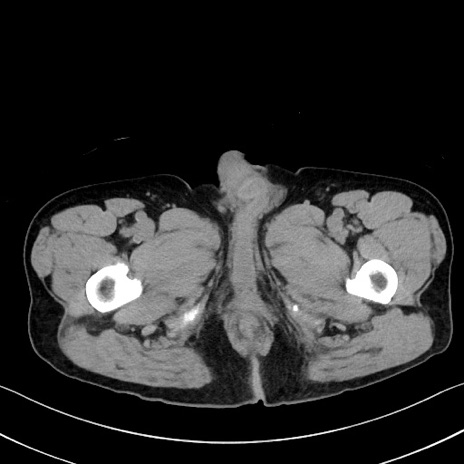

症例35(横断像)

【症例】70歳代 男性

【主訴】腹部膨満、嘔吐

【現病歴】昨日より腹部膨満感出現。本日増悪し、仙痛出現。嘔吐あり、受診。

【既往歴】糖尿病、胆摘後

【身体所見】BP 149/80mmHg、HR 74/min、BT 35.9℃、腹部:膨満、軟、圧痛なし。腸雑音減弱あり。上腹部正中切開瘢痕あり。

【データ】WBC 13500、CRP 1.72